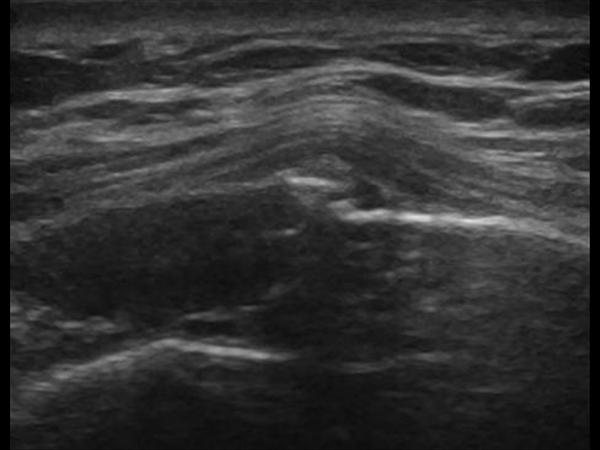

Gãy xương sườn

Gãy xương sườn - Ảnh 5

» Thông tin: Nữ giới – 52 tuổi.

» Lâm sàng: Chấn thương ngực.